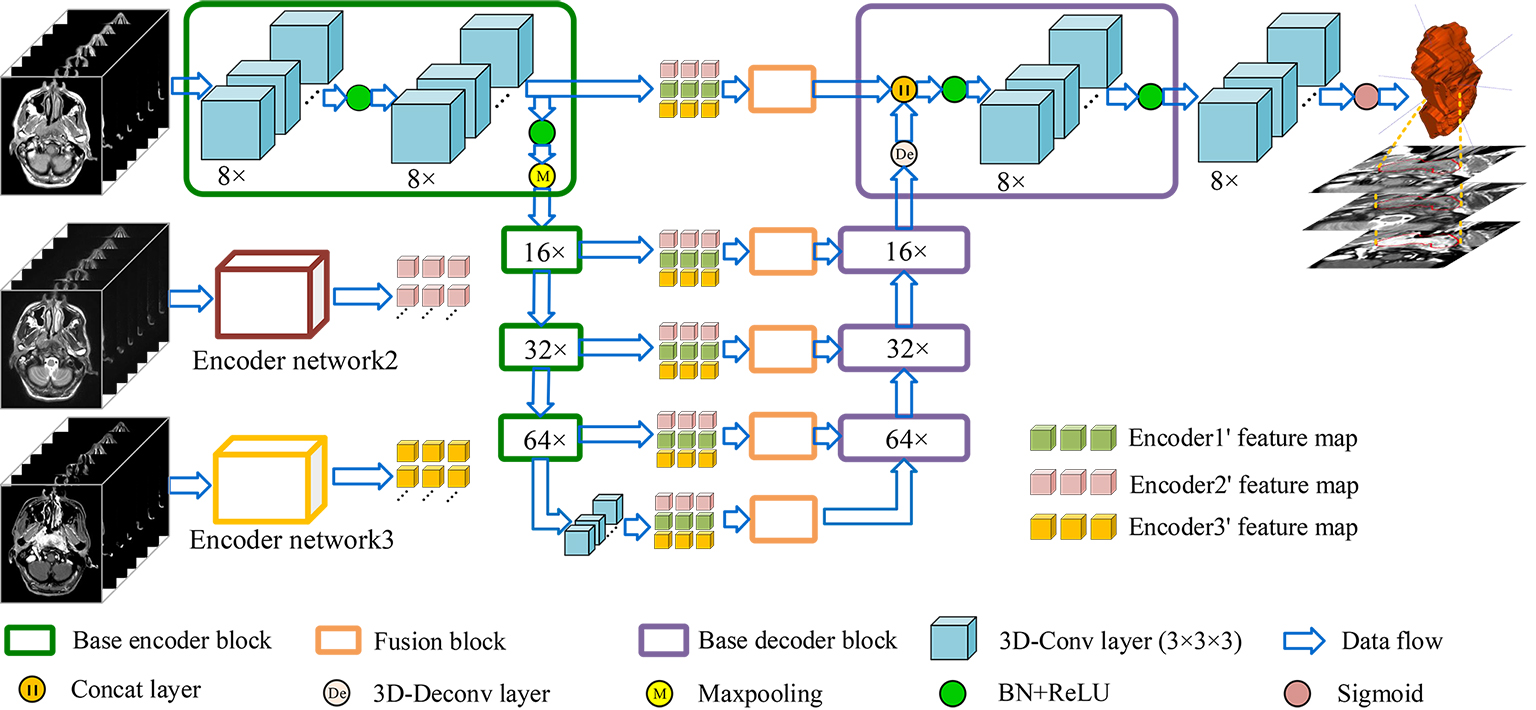

As illustrated in Figure 2, our framework is an end-to-end fully convolutional network, containing three encoders to take 3D images from three modalities of MRI as inputs. The encoder network is a VGG-liked [34] DNN, which stacks base block containing several 3D convolutional layers followed by max-pooling layers to get deeper features. And the decoder network uses 3D deconvolutional layers to upsample feature maps, the final output is a feature map with the same size as input. Both low-level features and high-level features, which are relevant to NPC segmentation, can be obtained by the design of multiple encoders and one single decoder. In order to effectively fuse low-level features from multi-modality MRI and keep balance between high-level and low-level features, a fusion block composed with 3D-CBAM and RFBlock is proposed to recalibrate and fuse multi-source low-level feature maps. For the training of network, we propose self-transfer to use pre-trained modality-specific encoders, which can capture individual modality-specific features from single modality MRI, as initial encoders of multi-modality model. The utilization of self-transfer can effectively improve the performance of encoders and make full mining of informative features from every modality of data.

3.1 Base encoder-decoder network

Inspired by U-net [35], our base encoder-decoder network can be seen as a U-net composed with 3D convolutional layers and 3D deconvolutional layers. Through stacking convolutional layers and max-pooling layers, encoder network can get larger receptive field, meanwhile, the spatial resolution becomes smaller. On the contrary, decoder network is composed with 3D deconvolutional layers to upsample feature maps, thus, the spatial resolution of features can recover to original scale when high-level features go through it. As described in [36], higher layers capture high-level representations, which are necessary for recognize targets, and lower layers capture low-level representations such as texture, which play major roles in reducing the missing of tiny structures when we segment objects. Therefore, both content and style representations should be utilized to complete NPC segmentation. Thus, skip connection layers are adopted to combine low-level and high-level features. The architectures of base encoder block and decoder block are illustrated in Figure 3.

Base encoder network. Our encoder network is a VGG-liked [34] network, and the base block is composed with two 3D convolutional layers. According to [37], the representation size should slightly decrease to avoid bottlenecks with enormous compression. Therefore, 3D convolutional layers and max-pooling layers are preferential choices to construct our network. And after convolution, a batch normalization layer and a ReLU layer are followed. There are two outputs produced by encoder block, one is for next encoder block, and the other one is for the corresponding decoder block to realize the combination of high-level and low-level features. There are totally four encoder blocks and the channel number of outputs () is 8, 16, 32 and 64 respectively. It is worth mentioning that there is one single convolutional layer after final encoder block to refine features downsampled by encoder block, and the number of its channels is 64.

Base decoder network. The purpose of decoder network is to map high-level features to target modality. A 3D deconvolotional layer is utilized to upsample feature maps, then, a concatenation layer combines these features with low-level features from encoders with the assistance of skip connection layers. After merging, a convolutional layer is adopted to fuse these feature maps. The numbers of output’s channels for decoder blocks are 64, 32, 16 and 8 respectively.

Finally, the final decoder block is followed by a convolutional layer with sigmoid as activation function to produce final segmentation results.

3.2 Fusion block

The purpose of fusion block is to effectively recalibrate and fuse low-level features from different modalities of MRI before merging them with high-level features. It is a hard task to directly fuse low-level features from multiple MRI, which vary greatly from each other due to the varied responses to different tissues of multi-modality MRI. Therefore, the fusion block will firstly re-weighting features and highlight regions that are greatly relevant to NPC with the assistance of 3D-CBAM. 3D-CBAM is composed with a channel attention block, which focuses on ’what’ are meaningful features, and a spatial attention block, which focuses on ‘where’ is an interesting part. After recalibrating low-level features, an RFBlock is utilized to fuse them into ones with the same channel number of corresponding high-level features to keep balance between them. The architectures of them are shown in Figure 4.

3.3 Self-transfer learning

Transfer learning [40], utilizing a powerful pre-trained network as features’ extractor, is a popular trick to improve performance of new systems. Hence, using a network pre-trained in imagenet as an encoder for a segmentation network is a common operation in natural images [41, 42]. However, there is not a powerful enough 3D pre-trained model can be set as the initial features’ extractor for various 3D medical images due to their complexity and various imaging technologies. Especially for multi-modality MRI, images of each modality have their own specific imaging styles, it’s hard to obtain a features’ extractor, which can be generalized to all of them. Additionally, by the design of multi-encoder single-decoder network, complementary information and cross-modal interdependencies can be extracted, while some individual features of specific modality may be ignored. To address these problems, we propose an initialization trick named self-transfer to effectively initialize encoders and make full mining of features of different modalities of MRI. According to experimental results, performance of multi-encoder-based models can obtain considerable improvements by using self-transfer.

Specifically speaking, a modality-specific model can effectively capture individual informative features from one single modality of data, while a multi-modality model aims to obtain interdependent and complementary information from multiple-modality datasets. As a result, some individual features of one single modality may be ignored in multi-modality model. Therefore, we propose self-transfer to fully mine modality-specific features. Figure 5 is the illustration of self-transfer. The first step is to respectively train three modality-specific encoder-decoder models. Then, these pre-trained encoders will be used as the initial encoders for multi-modality model. Compared to original encoders with random initialization, these encoders have greater power to make full mining of individual features from specific modality of MRI. Meanwhile, the fusion block and decoder can effectively fuse these features to obtain informative features for final predictions. We will set several experiments to demonstrate that self-transfer can enhance the segmentation systems in the following paper.